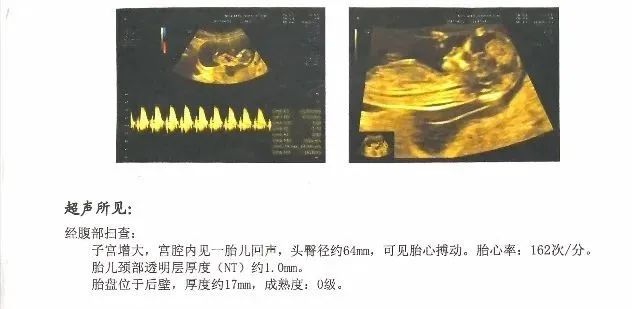

一般而言:妊娠5周阴道超声,可见清晰的卵黄囊和胚芽;妊娠6周可出现胎心搏动;有胎芽和胎心搏动声像就可以确定为临床妊娠;经腹超声检查有时因患者膀胱充盈不良或者腹部脂肪层过厚等原因可适当推迟1~2周进行;假如月经规律、排卵时间明确、估算胎儿大概8周以上经阴道超声仍然无心管搏动预示胚胎停止发育的可能性极大,因此,推荐首次的妊娠超声检查一般安排在妊娠7~8周左右比较适宜。根据β-HCG数值和首次超声检查的结果推算出妊娠11~13周的具体时间,提前预约胎儿NT(颈后透明膜厚度),该项检查是胎儿的第一次排畸筛查,若增厚可能与胎儿神经管发育异常,染色体异常等相关,所以提醒各位准妈妈务必提前预约(我院需提前至少4周时间预约),请勿大意漏检!

妊娠12周腹部超声胎儿NT图像示例